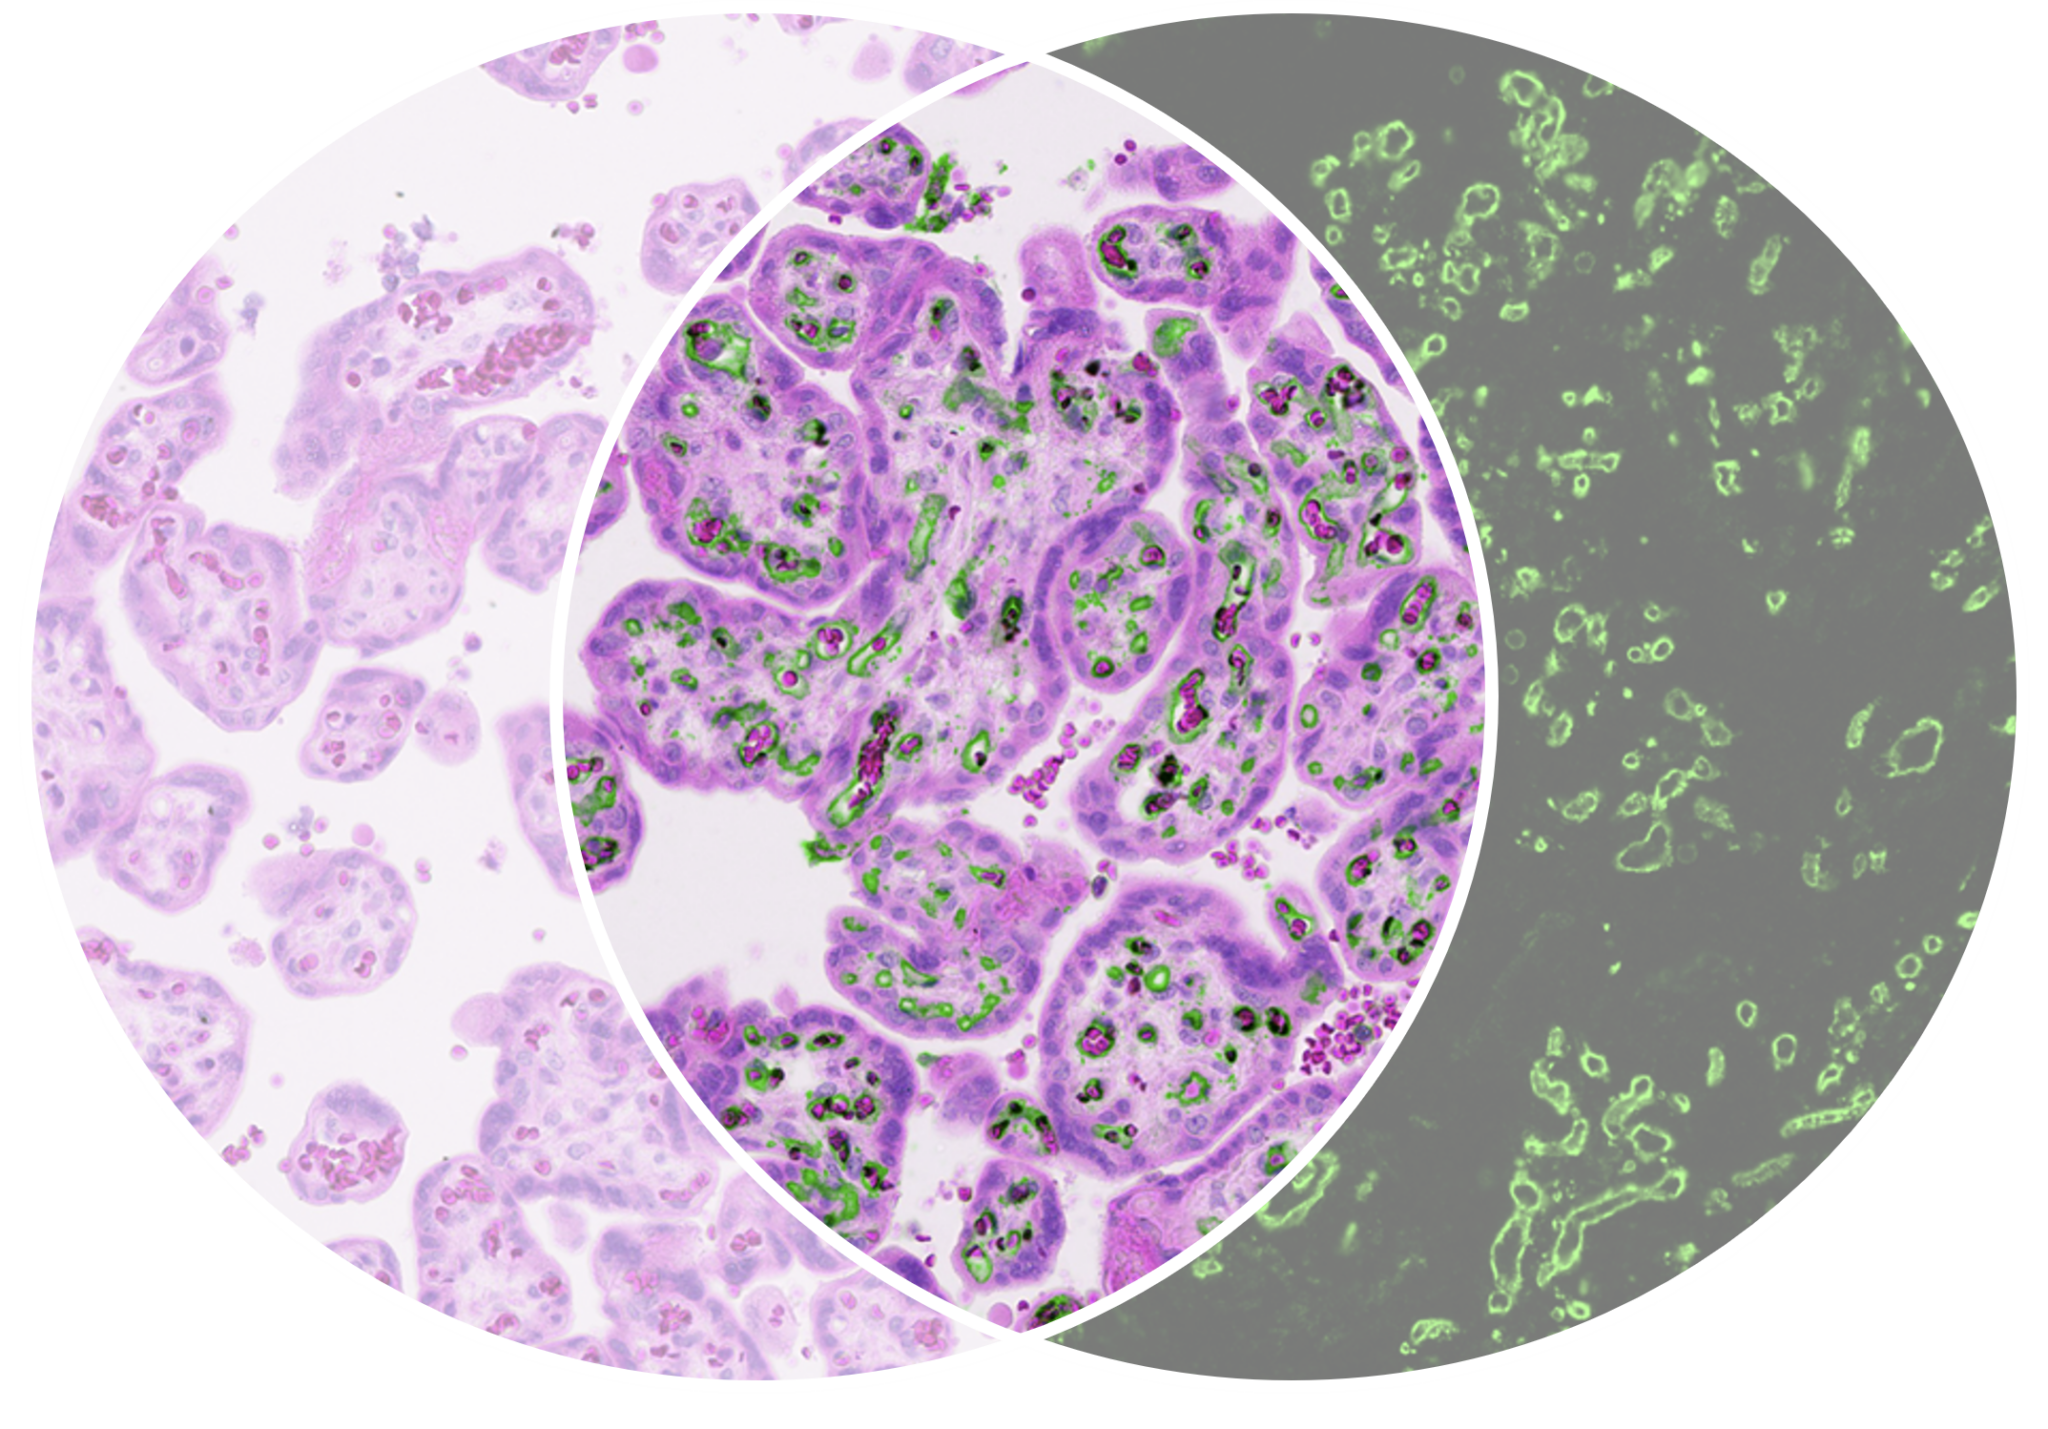

We have developed the next-generation IHC tissue analysis system, based on upconverting nanoparticles (UCNPs). The Lumito SCIZYS is a cutting-edge, high-sensitivity system combining labeling and imaging technologies to locate and measure biomarkers in tissue samples.

Struggling to quantify low‑abundance biomarkers in tissue? SCIZYS enables ultra‑sensitive, autofluorescence‑free detection, with a wide dynamic range in a single image. Move beyond visual scoring.

Detection of single labels from photon-upconverting nanoparticles

Chromogenic counterstain and biomarker information in fully separated channels from the same sample

High-accuracy quantification based on uniform nanoparticle light quanta and a wide dynamic range detection system